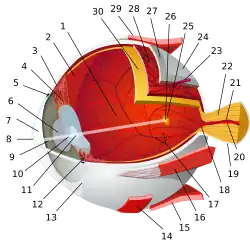

Человеческий глаз

Человеческий глаз фокусирует свет на слой фоторецепторных клеток, называемый сетчаткой, который образует внутреннюю поверхность задней части глаза. Фокусировка осуществляется серией прозрачных материалов. Свет, попадающий в глаз, сначала проходит через роговицу, которая обеспечивает большую часть оптической силы глаза. Затем свет проходит через жидкость сразу за роговицей — в переднюю камеру, а затем проходит через зрачок. Затем свет проходит через линзу, которая дополнительно фокусирует свет и позволяет регулировать фокусировку. Затем свет проходит через основной объём жидкости в глазу — стекловидное тело — и достигает сетчатки. Клетки сетчатки покрывают заднюю часть глаза, за исключением места выхода зрительного нерва; это приводит к существованию слепого пятна.

Есть два типа фоторецепторных клеток, палочки и колбочки, которые чувствительны к различным аспектам света[71]. Стержневые клетки чувствительны к интенсивности света в широком диапазоне частот, поэтому отвечают за чёрно-белое зрение. Клетки палочек не присутствуют в ямке, области сетчатки, ответственной за центральное зрение, и не так чувствительны, как клетки колбочек, к пространственным и временным изменениям света. Однако в сетчатке имеется в двадцать раз больше стержневых клеток, чем колбочек, поскольку стержневые клетки расположены на большей площади. Из-за чего стержни отвечают за периферическое зрение[72].

Напротив, колбочки менее чувствительны к общей интенсивности света, но бывают трёх разновидностей, которые чувствительны к разным частотным диапазонам и, таким образом, используются для восприятия цвета и фотопического зрения. Конусные клетки сильно сконцентрированы в ямке и отвечают за высокую остроту зрения, что означает, что они имеют лучшее пространственное разрешение, чем палочки. Поскольку колбочки не так чувствительны к тусклому свету, как палочки, в большинстве случаев за ночное зрение отвечают палочки. Точно так же, поскольку клетки колбочек находятся в ямке, центральное зрение (включая зрение, необходимое для чтения, работы с мелкими деталями, например шитья или тщательного изучения объектов) осуществляется колбочками[72].

Ресничные мышцы вокруг хрусталика позволяют регулировать фокусировку глаза. Этот процесс известен как аккомодация. Близкая точка и дальняя точка определяют ближайшие и отдалённые расстояния от глаз, при котором объект может быть рассмотрен в фокусе. Для человека с нормальным зрением дальняя точка находится в бесконечности (горизонте). Расположение ближайшей точки зависит от того, насколько мышцы могут увеличить кривизну хрусталика, и насколько негибким стал хрусталик с возрастом. Оптометристы, офтальмологи и оптики обычно считают подходящую близкую точку ближе, чем нормальное расстояние для чтения — примерно 25 см[71].

Дефекты зрения можно объяснить с помощью оптических принципов. С возрастом хрусталик становится менее гибким, и ближняя точка отдаляется от глаза — состояние, известное как пресбиопия. Точно так же люди, страдающие дальнозоркостью, не могут уменьшить фокусное расстояние своих хрусталиков до такой степени, чтобы на их сетчатке отображались близлежащие объекты. И наоборот, люди, которые не могут увеличить фокусное расстояние своих хрусталиков до такой степени, чтобы на сетчатке отображались удалённые объекты, страдают миопией и имеют дальнюю точку, которая значительно ближе, чем бесконечность (горизонт). Состояние, известное как астигматизм, возникает, когда роговица не сферическая, а более изогнута в одном направлении. Это приводит к тому, что горизонтально вытянутые объекты фокусируются на разных частях сетчатки, отличными от частей на которых фокусируется изображение вертикально вытянутых объектов, что приводит к искажению изображений[71].

Все эти состояния можно исправить с помощью корректирующих линз. При пресбиопии и дальнозоркости собирающая линза обеспечивает дополнительную кривизну, необходимую для приближения ближней точки к глазу, в то время как при миопии расходящаяся линза обеспечивает кривизну, необходимую для отправки дальней точки в бесконечность. Астигматизм корректируется с помощью линзы с цилиндрической поверхностью, которая сильнее изгибается в одном направлении, чем в другом, что компенсирует неоднородность роговицы[73].

Оптическая сила корректирующих линз измеряется в диоптриях, то есть величинах, обратных фокусному расстоянию, измеренному в метрах; с положительным фокусным расстоянием, соответствующим собирающей линзе, и отрицательным фокусным расстоянием, соответствующим рассеивающей линзе. Для линз, которые также корректируют астигматизм, даны три числа: одно для сферической оптической силы, одно для цилиндрической оптической силы и одно для угла ориентации астигматизма[73].